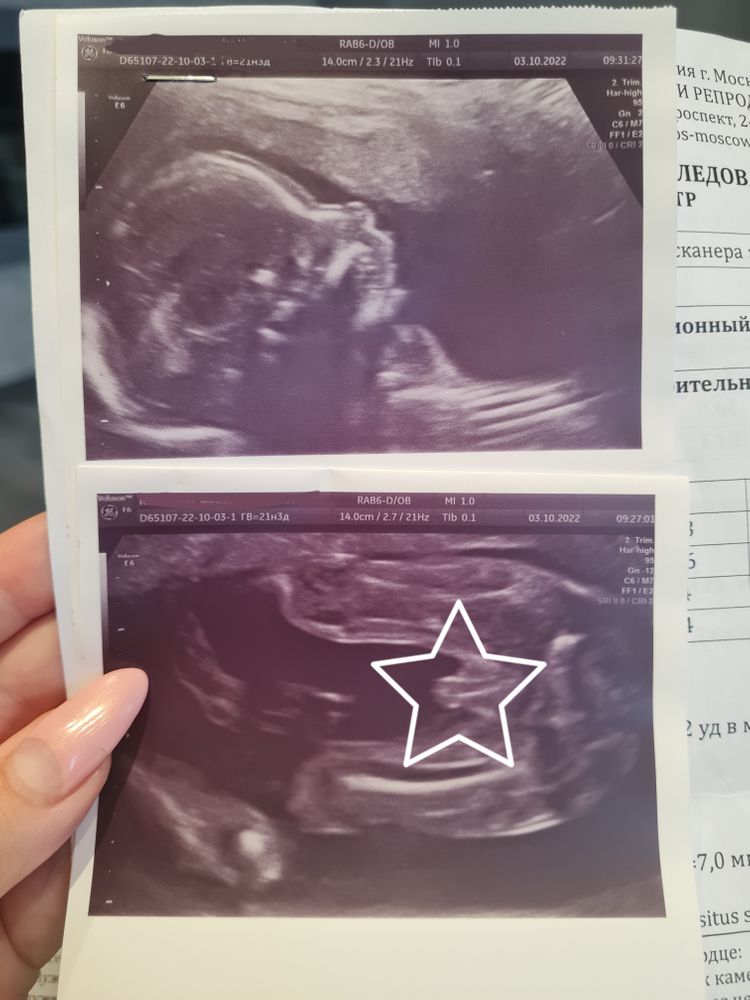

3) Про замеры малыша и пол вообще интересно. Пока все 4 разных доктора мне хором не сказали про мальчика - ничему не верила, знаем мы прецеденты))

Последний, так вообще - первые минут 10 делал мне фото писюна в разных ракурсах и проекциях (и 3D, и просто узи). Смешно)) Врачом мужчина был, кстати.

Вот вам фото писюна, вдруг кому интересно как он выглядит в 21 неделю)))